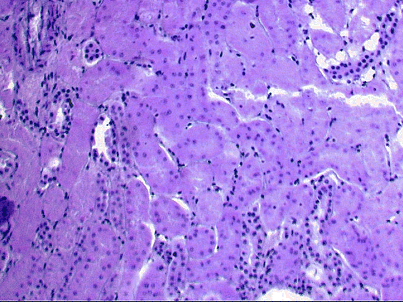

Зернистая дистрофия, или мутное набухание печени, вид белковой дистофии, характеризующийся появлением в цитоплазме клеток зерен и капель белковой природы. В этот дистрофический процесс вовлекаются паренхиматозные органы (печень(рис.1, 1а), почки (рис.2), миокард), реже скелетные мышцы. Этот вид дистрофии наиболее часто развивается при острых инфекционных и септических заболеваниях с/х животных. Таких как сибирская язва, пастереллез, рожа, свиней, колибактериоз и др. при вирусных заболеваниях (чума свиней, птиц, ящур, ЗКГ и др.).

Рис.1. Зернистая дистрофия печени.

Микроскопические признаки зернистой дистофии характеризуются набуханием (увеличением клеток и зерностостью цитоплазмы, уменьшаются просветы внутридольковых синусоидных капилляров; цитоплазма печеночных клеток становится мутной, богатой гранулами или каплями, белковая природа которых определяется гистохимичечкими методами.

Рис.2. Зернистая дистрофия печени.

Макроскопически органы при зернистой дистрофии набухшие, дряблой консистентности, окрашены бледнее, чем в норме. На разрезе паренхима выбухает за капсулу, поверхность разреза тусклая, суховатая. Сердечная скеленая мышца напоминает ошпаренное кипятком мясо, а печень и почки серовато-бурый цвет.